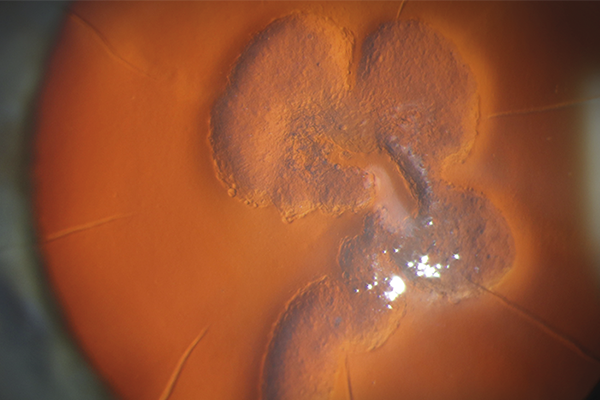

Duke at Retina Society 2024

The 57th annual meeting of the Retina Society was held September 11-15, 2024 in Lisbon, Portugal. Several Duke Retina Faculty and trainees participated in the meeting, including Durga Borkar, MD, MMCi, Sharon Fekrat, MD, FACS, FASRS, Majda Hadziahmetovic, MD, Glenn Jaffe, MD, Eleonora Lad, MD, PhD, Cynthia Toth, MD, Lejla Vajzovic, MD, FASRS, Michalis Georgiou, MD, PhD, Tammy Hsu, MD, Mustafa Iftikhar, MD, Angela Li, MD and Hemal Patel.